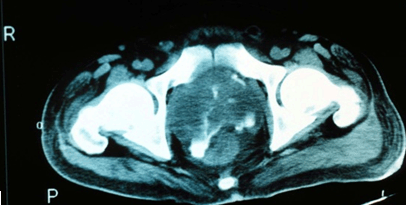

Acute cases are those where symptoms were present for less than 2 months. In most patients, mean incubation was 9 days (range 1-21 days), although cases up to 62 years after initial exposure have been reported35. The spectrum of clinical presentations range from the severe, fulminant disease (such as multi-organ abscesses) to asymptomatic or minor localised infections. The type of presentation may be influenced by the magnitude of exposure, mode of acquisition, host factors and risk factors. Melioidosis may present as pneumonia, skin abscesses, internal organ abscess, osteomyelitis, septic arthritis and even encephalomyelitis2. Almost any organ system may be affected, including the lungs, kidneys, prostate, skin, liver, parotids and the brain20,36,37. In the Australian context, acute melioidosis accounts for a large majority of presentations (up to 91% compared to 9% for chronic disease)38. It is interesting to note that B. pseudomallei prostatic abscesses (Fig1), which had been thought of as uncommon, have been shown to be prevalent in Australian patients37,39. This range of unusual pathologies due to melioidosis demonstrates the need to perform extensive investigations in affected patients.

Figure 1: MRI showing Burkholderia pseudomallei prostatic abscess (courtesy Dr Robert Norton, Director of Pathology, Townsville Hospital).